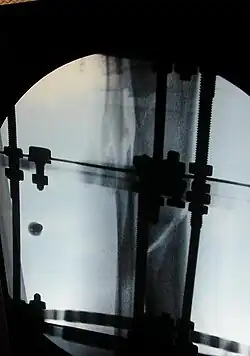

The photographs and radiographs illustrate the application and emplacement of an external fixator, an Ilizarov apparatus, to repair the open fracture of the lower left leg of a man. The photographs were taken four weeks after the patient fractured the shinbone (tibia) and the calfbone (fibula) of his left leg, and two weeks after the surgical emplacement of the Ilizarov apparatus to immobilise the leg and isolate the wound and fracture site to facilitate healing.

X-ray of the callus forming at the fracture site, three months post-fracture; perspective 3-4. -

X-ray of the callus forming around the fracture site, three months post-fracture; perspective 4-4. -